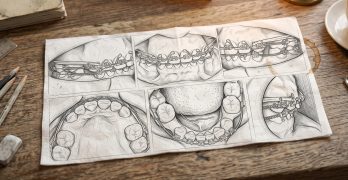

El artículo se centra en la importancia crítica de la colocación de los brackets en el tratamiento de ortodoncia, … [Leer más...] acerca de Posicionamiento Estratégico de Brackets: Cuándo Desviarse del Protocolo para Resultados Superiores

Posicionamiento Estratégico de Brackets: Cuándo Desviarse del Protocolo para Resultados Superiores

Baja las guías de posicionamiento de brackets del Dr. Tom Pitts